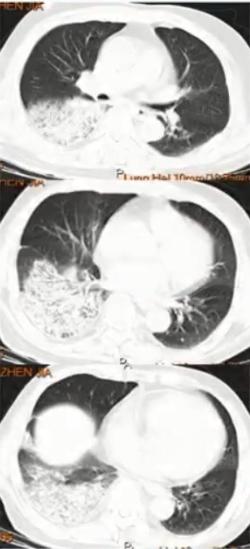

图1 患者的影像学以实变为主